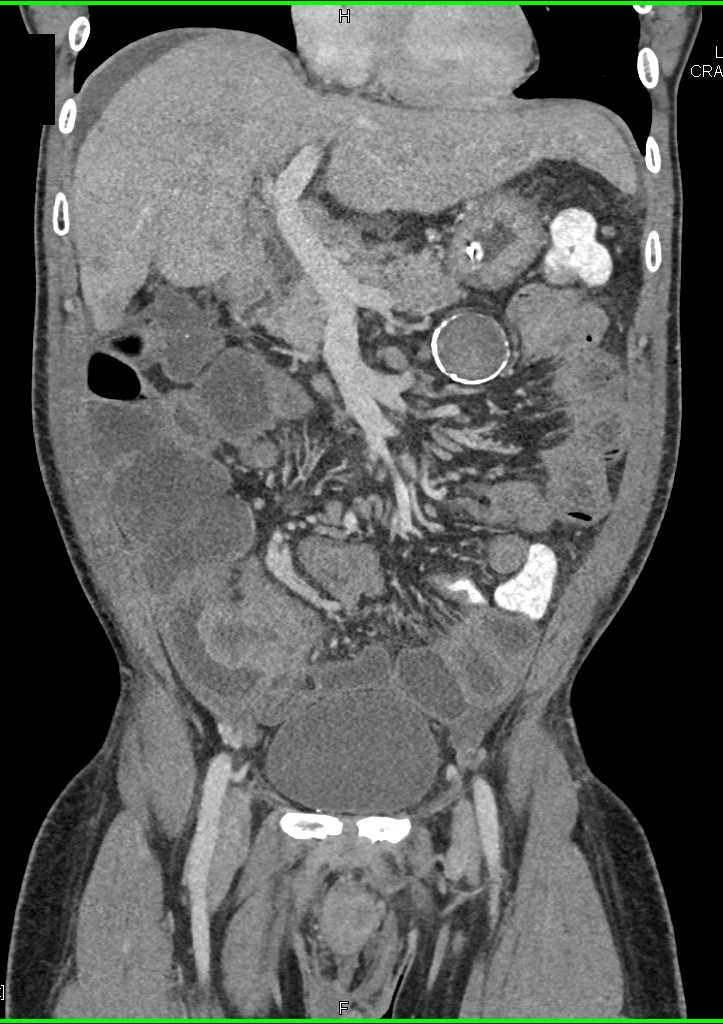

Small Bowel Carcinoma with Carcinomatosis